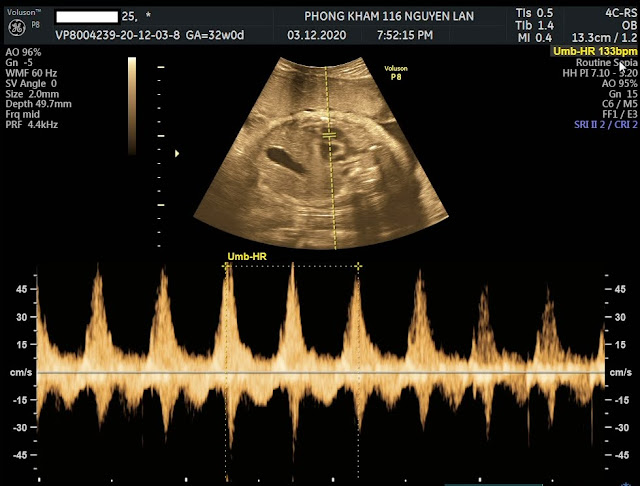

3. Thai nhi 32 tuần tuổi có nên siêu âm 4D, 5D không?

- Đây là tuần thai vô cùng cần thiết mà bé đã hình thành rõ

nét một số cơ quan bộ phận để bác sĩ có thể kiểm tra xem con có bị dị tật hay

các vấn đề gì khác hay không nên mẹ hãy đi siêu âm 4D, 5D ở tuần thai thứ 32 nhé!

- Tại tuần này, khi siêu âm bác sĩ sẽ:

- Đánh giá lại tổng thể hình thái thai nhi , khẳng định các đị tật. Ngôi thai ( Tư vấn ngôi thai)

- Xác định trọng lương thai (Thai nhỏ, chậm tăng trưởng, tư vấn đinh dưỡng, tư vấn sinh, tư vấn và phân tích kết quả HSS.

- Đánh giá tình trạng nưới ối (Tư vấn để giữ ối đủ)

- Đánh giá tình trạng bánh rau (Tư vấn dinh dưỡng)

- Đánh giá dây rau, quấn cổ, sa dây rau đối với ngôi ngược. Tình trạng dây rau bám nép, bám màng, rau bong non.